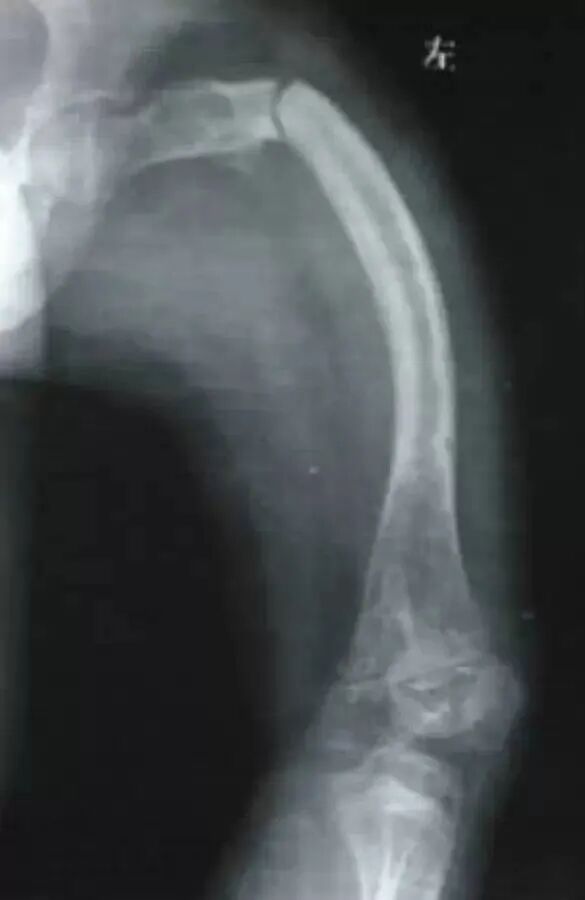

入院检查:患者男性,16岁,因“外伤致右大腿肿痛伴活动受限2天”;体查:平时坐轮椅生活,身高: 132cm,体重: 43kg,蓝巩膜,双下肢弯曲畸形,X形腿右下肢石膏固定,右大腿稍肿胀,压痛,可及骨擦感。辅查:本院X线及CT(见图一):右股骨干下段骨折,骨质疏松,双下肢弯曲畸形,胸片及ECG无明显异常;其他:既往史无特殊,父母及1兄弟均无遗传病史。

图一:入院X线及CT

入院诊断:1.右侧股骨干下段骨折伴双下肢畸形2.成骨不全症 3.继发性骨质疏松

治疗方案:1.右侧股骨干骨折伴畸形多段截骨矫形髓内钉固定术2.左侧股骨干畸形多段截骨矫形髓内钉固定术。